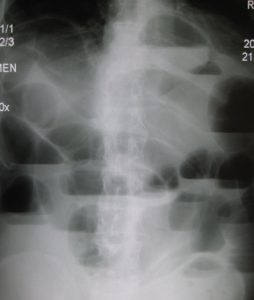

- гастрит; патології жовчовивідних шляхів; виразкові коліти; непрохідність кишечнику; запальний процес в сегментах травної системи та ін;

Непрохідність кишечника - розлади в органах грудної клітки (кісти; пухлини; бронхіт, травми; аневризми аорти; запалення легенів; зоб та ін);

Непрохідність кишечника